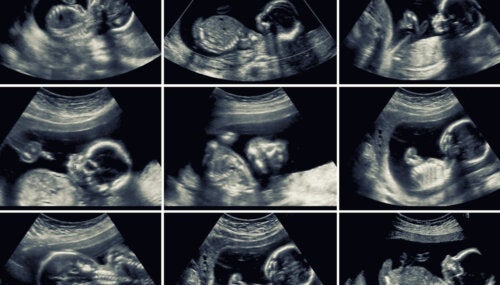

De fases van een zwangerschap

Je lichaam verandert elke week, je baby groeit en er gebeurt nog zoveel meer in je lichaam dan je ooit had verwacht. Een zwangerschap is een ongelooflijk proces, een wonder dat we aan je zullen uitleggen, praktisch en van dichtbij, zodat je volop van deze tijd kunt genieten.